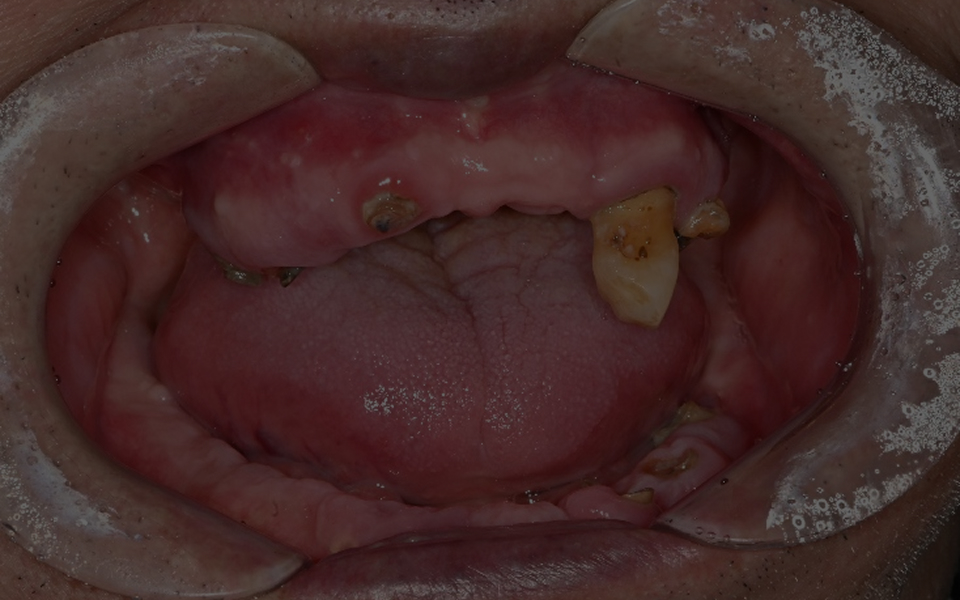

CASE 02 김** / 60대

전악임플란트

치료 시작 전 촬영 2024.01.24 | 치료 완료 후 촬영 2024.12.26

1 예후불량 치아 발치

2 발치 후 즉시 임플란트 식립 및 뼈이식

3 고정성 보철물로 수복 후 일상 회복